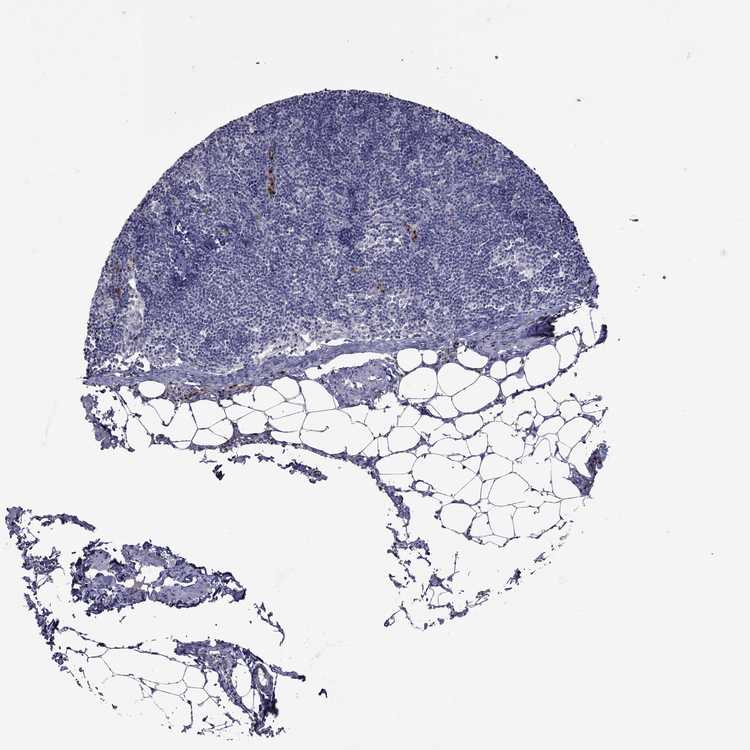

TISSUE PRIMARY DATA LYMPH NODE Show tissue menu

Lymph node

LYMPH NODE - Expression summary

LYMPH NODE - Antibody stainingi

Antibody staining in the annotated cell types in the current human tissue is reported as not detected, low, medium, or high, based on conventional immunohistochemistry profiling in selected tissues. This score is based on the combination of the staining intensity and fraction of stained cells.

Each image is clickable and will lead to virtual microscopy that enables deeper exploration of all samples and also displays staining intensity scores, fraction scores and subcellular localization as well as patient and tissue information for each sample.

Antibody HPA046700Antibody HPA076024

Germinal center cells Medium-

Non-germinal center cells HighMedium